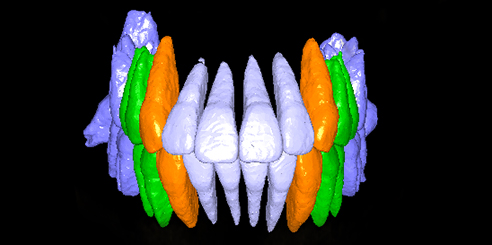

Model Scan (Optional) – Dental CBCT Support

In addition, optional model scanning allows accurate digital impressions and prosthetic planning, making this system ideal for both orthodontic and implant applications.

Furthermore, AI+PAN Dental CBCT Imaging enhances precision.

- The system rebuilds panoramic views directly from CBCT data using AI.

- Panoramic auto-focus and multi-layer technology select the best curve automatically.

- Therefore, the final image is cleaner and easier to read.